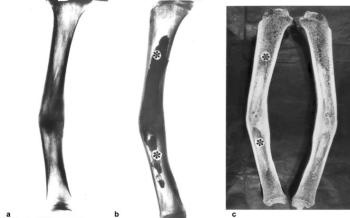

5. Kontrasztanyagos rtg-felvétel a diagnosztikában (pl. gyomor – epehólyag, vese – húgyutak radiológiai ábrázolása, angiográfia stb.) mindennapos. A paleoradiológiában a belszervek vizsgálatára nincs mód, a sugárfogó anyag használata jószerivel csak a csontfis tulák, csonttályogok esetében lehetséges. A paleoradiológia speciális igényeinek megfelelő fistulográfiás módszert dolgoztunk ki (Józsa és Ferencz 1991), amellyel sikerrel tüntettük fel a csonttályogokat és sequestereket (32. ábra).

32. ábra. 12–13. századból származó tibia. a) Tengelyeltéréssel gyógyult tibia rtg-felvételén vaskos callus látszik. b) A sipolyjáraton át kontrasztanyaggal feltöltött csont velőüregében kiterjedt tályogrendszer (csillag) ábrázolódik a rtgképen. b) A felfűrészelt csontban a hídcallus két oldalán elhelyezkedő tályogüregek figyelhetők meg